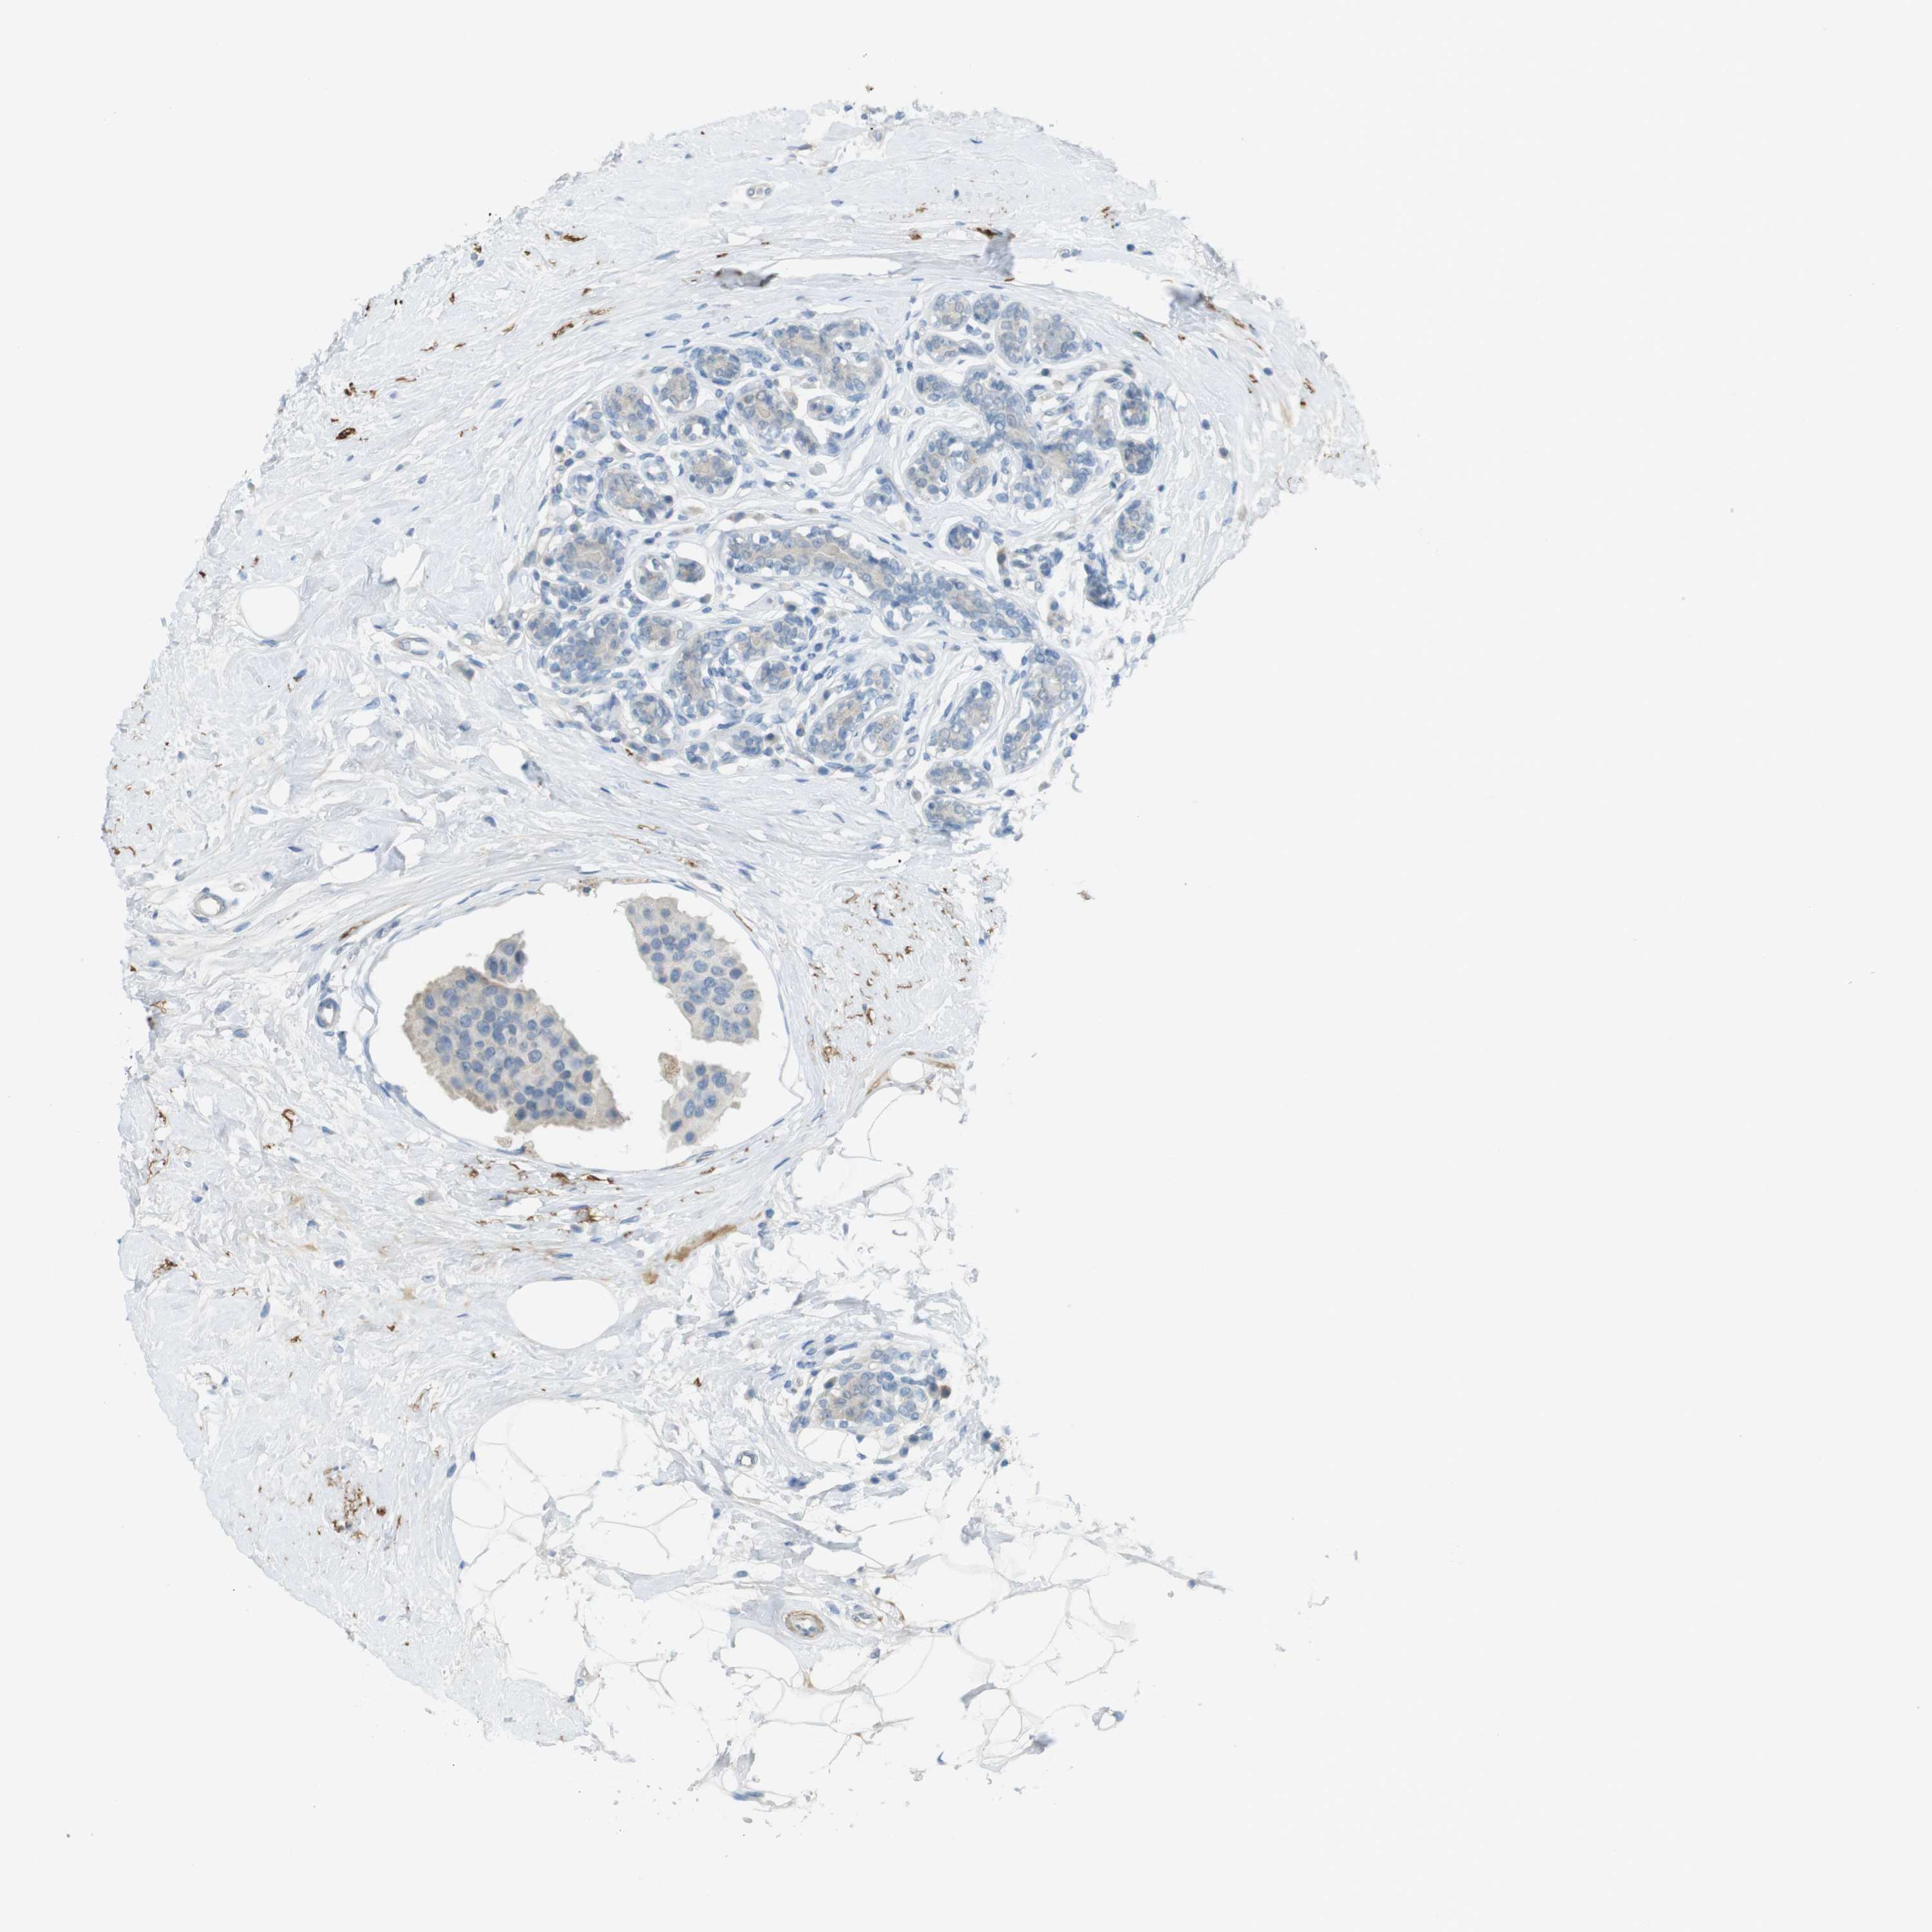

CANCER BREAST CANCER Show tissue menu

BRCA TCGA BRCA VALIDATION PROTEIN EXPRESSION

ANTIBODIES

AND

VALIDATION